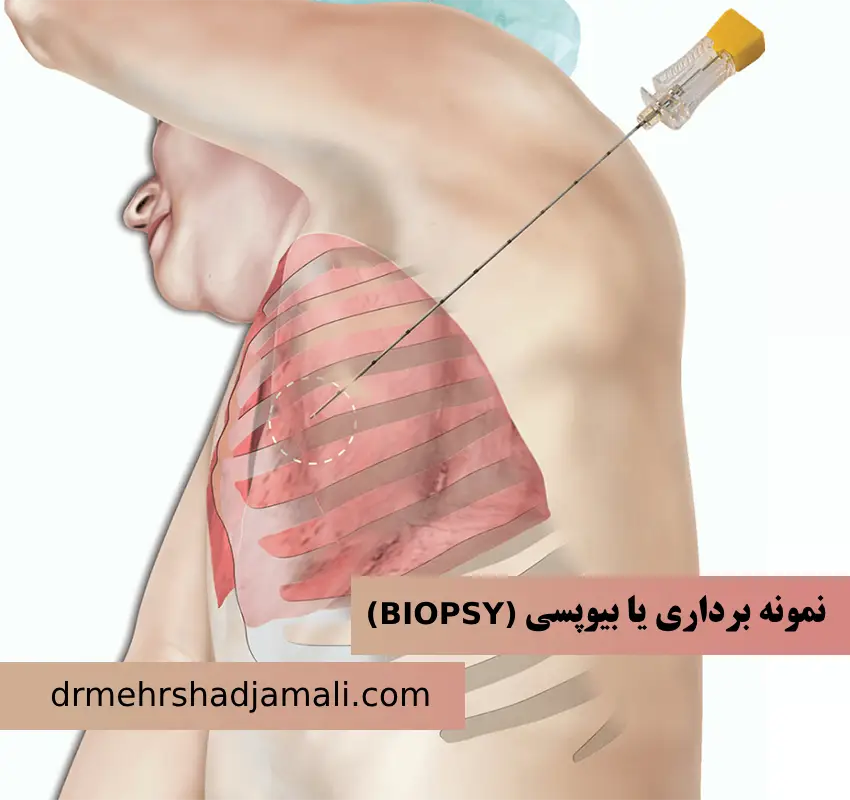

نمونه برداری یا بیوپسی (BIOPSY)

بیوپسی روشی برای بررسی دقیق تر بافت های بدن است که مشکوک به ابتلا به بیماری هستند، که به آن تکهبرداری و نمونهبردا�